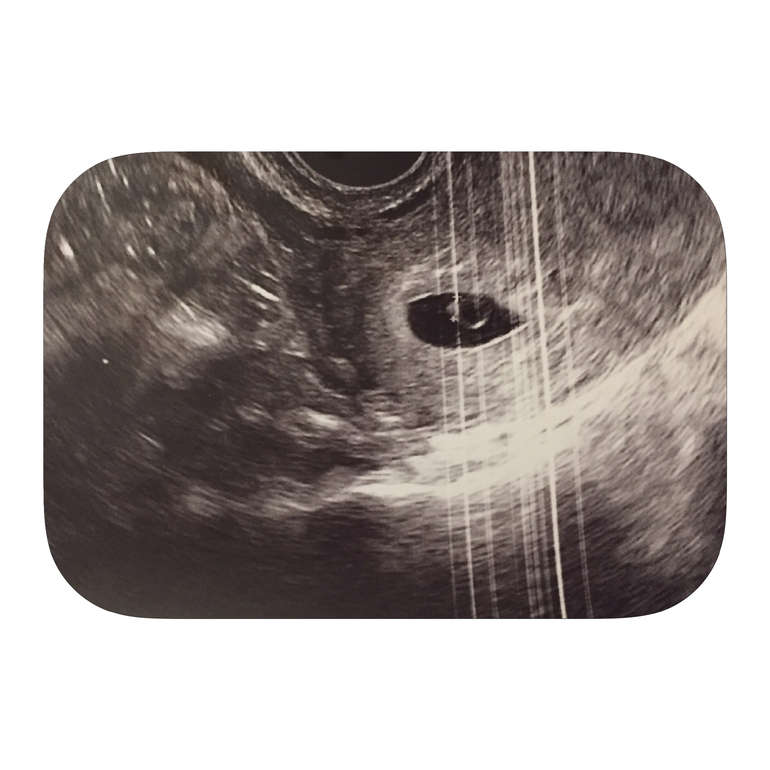

ФолликулометрияСегодня была на узи! Нашли крошечного эмбриона и сб! Врач сказала все хорошо! Не видили раньше, потому что очень поздняя О. Поэтому девочки, если у вас в 7 недель не увидели эмбриона, то это не страшно, правильно говорят, на узи лучше в 8 недель. Но все же, хоть меня и помучили, но я все равно счастлива! Видеть на экране как бьется сердечко уже крохотного человечка и слова врача "все хорошо" это просто прекрасно! Итак по месячным срок сегодня 7 недель и 6 дней, по узи ровно 6 недель!

Ну и фото на память (фото не очень так как аппарат старый)